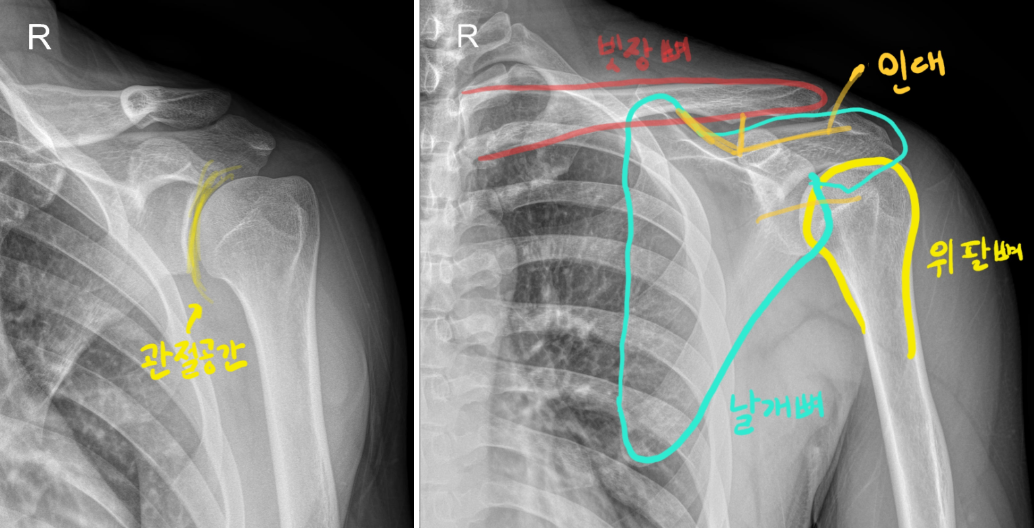

°Ë»ç ÀÌÈÄ ¿ì¸®´Â X-ray °Ë»ç¸¦ ÁøÇàÇÕ´Ï´Ù.

X-ray °Ë»ç¸¦ Çϸé À§¿Í °°Àº »çÁøÀ» ¾òÀ» ¼ö ÀÖ½À´Ï´Ù.

¿À½Ê°ßÀÌ ÀǽɵǴµ¥ X-ray¸¦ °Ë»çÇÏ´Â ÀÌÀ¯´Â ´Ù¸¥ Áúȯ

¿¹¸¦ µé¾î ¼®È¸È­, ȸÀü±Ù°³ÁõÈıº, ¾î±úÃæµ¹ÁõÈıº µîÀ» °¨º°Çϱâ À§ÇÔÀÔ´Ï´Ù.